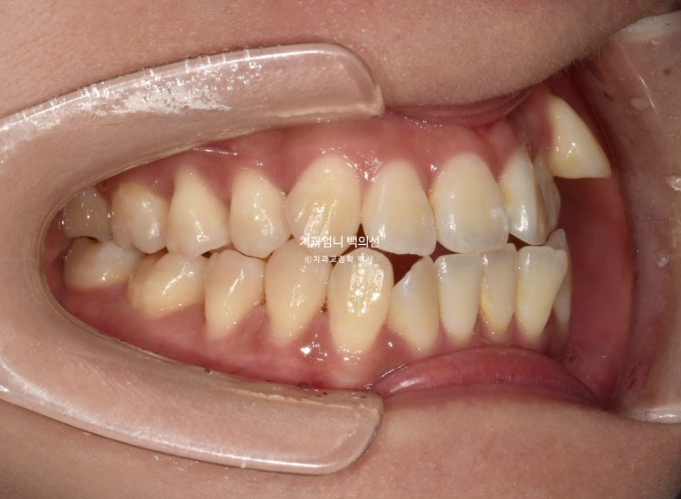

23년 8월, 교정치료를 위해 내원한 환자분입니다.

고치고 싶은 것은 단 하나 <덧니> 였습니다.

23.09

왼쪽 송곳니 하나가 완전히 배열에서 벗어나 있습니다.

덧니가 있으면 덧니쪽으로 중심선이 쏠리기 마련입니다.

위 앞니 중심선이 덧니쪽으로 틀어져 있는 것이 보입니다.

송곳니가 덧니가 제자리로 들어올 공간이 단 1mm도 없습니다.

심한 덧니입니다.

앞니는 윗니가 아랫니를 덮지 못하고 거꾸로 물리는 반대교합과 절단교합이 보입니다.

이 경우 입을 다물때 아랫입술이 나와보이고 입매가 부자연스럽습니다.